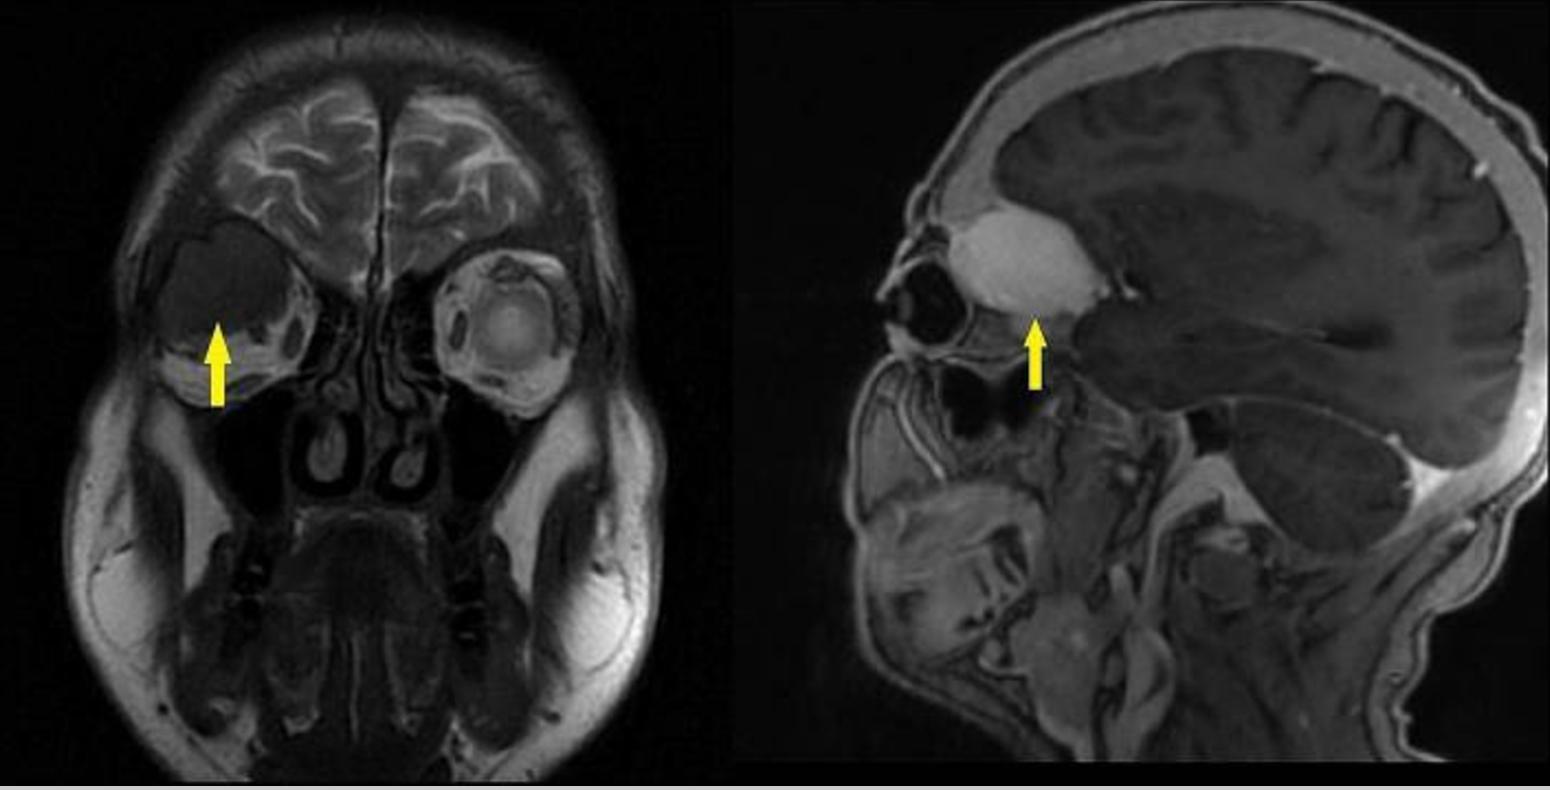

磁共振成像(MRI)眼眶和颅骨检查发现在右眼眶后外侧一个眶外肿块。肿块压迫额骨眶部、右侧视神经和上直肌。病变尺寸为36*27*24mm,MRI表现出弥散均匀对比增强。肿瘤病变在T1加权图像上表现为轻微高信号,在T2加权图像上显示为低信号。MRI如图1所示。CT扫描显示,右侧眼眶后外侧有一个膨胀性肿块,伴有外周线性钙化,起源于蝶骨翼(图2)。肿块病变导致相邻骨结构侵蚀,被归类为BT。

图1 大脑MRI图像。黄色箭头指向右眶后上外侧位置的眶外肿块病变